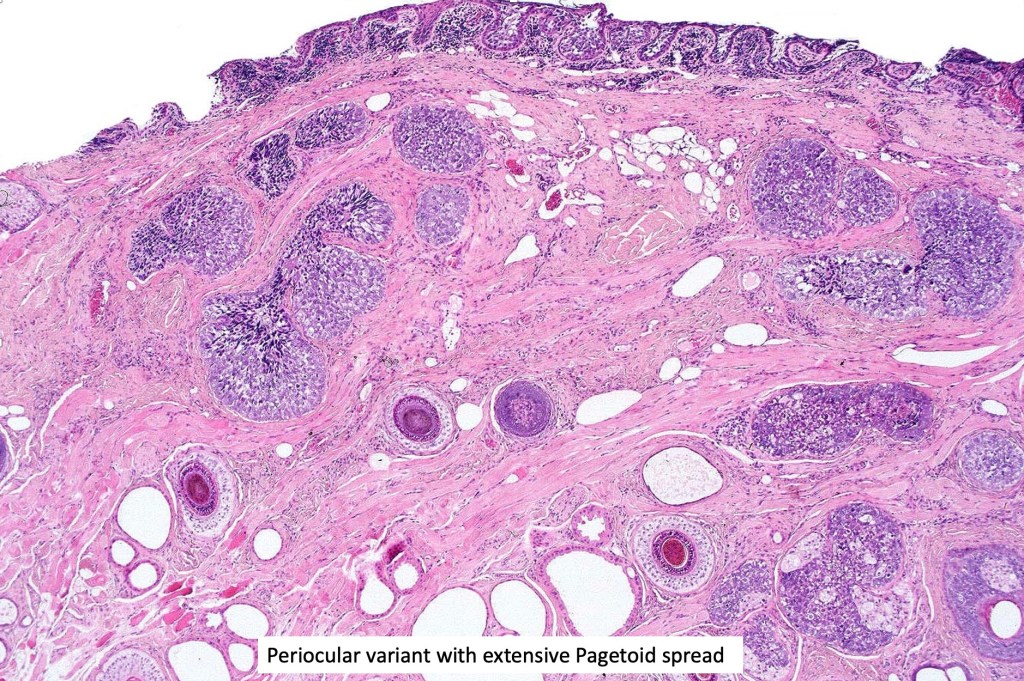

•Well differentiated lobular growth pattern though to a poorly differentiated tumor often showing a diffuse, infiltrating border which may extend into the subcutaneous fat

•Comedo type necrosis commonly present

•May be associated with Pagetoid spread

•Tumors are composed of an admixture of darkly staining basaloid cells with hyperchromatic or vesicular nuclei and more obvious sebaceous cells with eosinophilic, bubbly, multivacuolated cytoplasm frequently indenting the nucleus (scalloped)